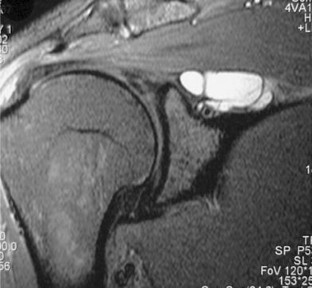

Fig. 3